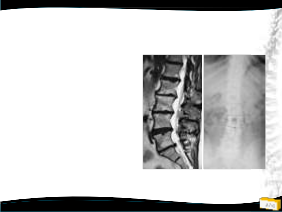

2009 2011

2011

Tedavi ?

– Konservatif

– Cerrahi

• Teknik?